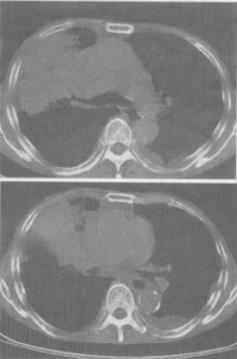

男,68岁,胸闷,咳痰,咯血2月余,胸部CT如图,最可能的诊断为()。

A、右上肺不张

B、右肺中央型肺癌

C、右上肺炎

D、右上肺肉瘤

E、肺炎性假瘤

B